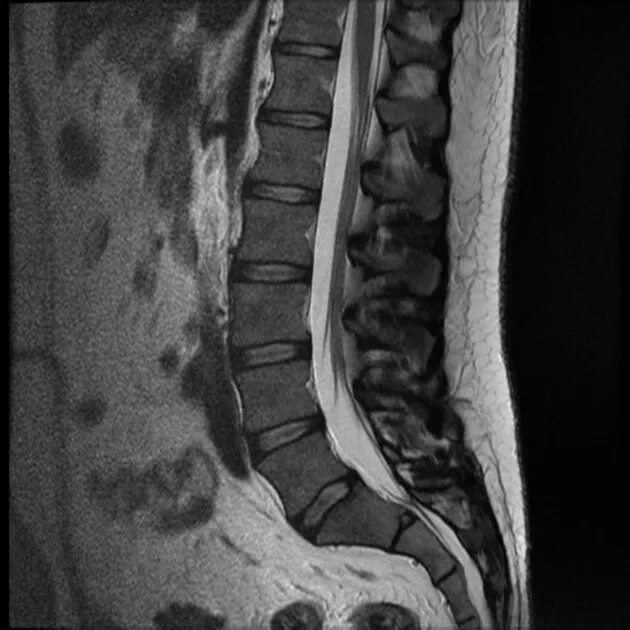

Мрт шейно поясничного отдела